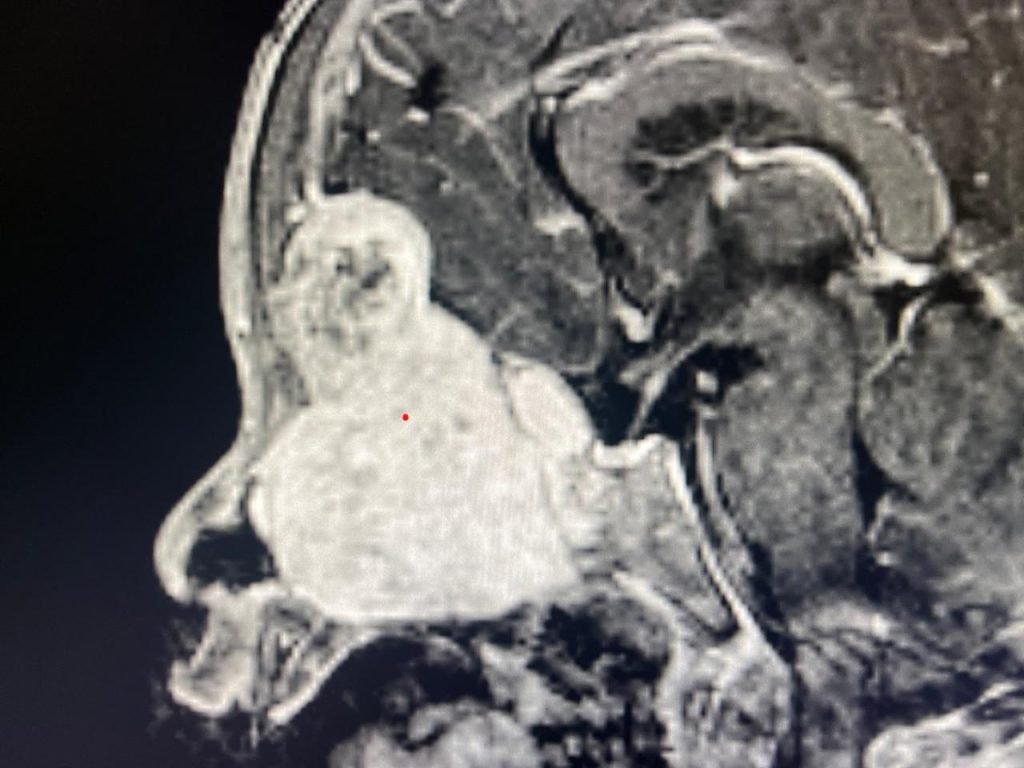

हरियाणा के सोनीपत निवासी यह बच्चा बाईं आंख के असामान्य रूप से बाहर निकलने, आंखों की गति में कमी, तेज खर्राटे, बाईं नाक से बाहर दिखने वाली गांठ और आंखों से अत्यधिक पानी आने जैसी गंभीर समस्याओं के साथ पीजीआई में भर्ती हुआ था। सीटी और एमआरआई जांच में सामने आया कि बच्चे के सिर के अगले हिस्से में 7 सेंटीमीटर का विशाल ट्यूमर है, जो नाक, साइनस, मस्तिष्क और आंख के कक्षक (ऑर्बिट) तक फैल चुका है। बायोप्सी में इसकी पुष्टि मेनिंगियोमा के रूप में हुई, जो बच्चों में अत्यंत दुर्लभ माना जाता है।

लगभग 9 घंटे तक चली इस जटिल सर्जरी में ट्यूमर को पूरी तरह नाक के रास्ते एंडोस्कोपी से सुरक्षित रूप से निकाल दिया गया, जिससे ओपन न्यूरोसर्जरी की आवश्यकता नहीं पड़ी। ट्यूमर के कारण खोपड़ी के आधार में बने बड़े दोष की कई परतों में मरम्मत की गई। सर्जरी के बाद बच्चे की हालत में उल्लेखनीय सुधार है और एमआरआई जांच में ट्यूमर के पूर्ण निष्कासन की पुष्टि हुई है।